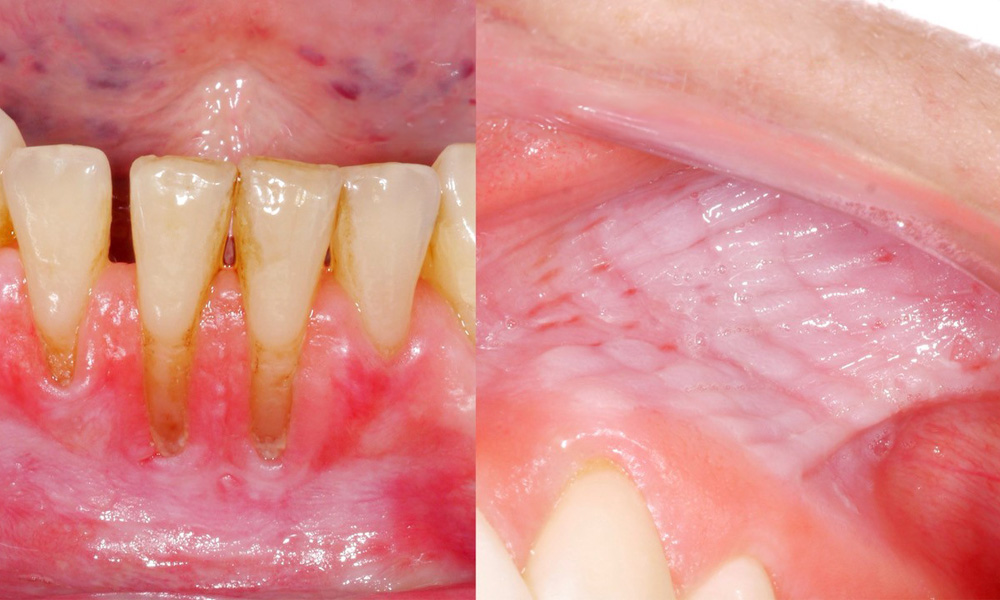

Snus verursacht Schleimhautläsionen & Gingivarezessionen

Es zeigte sich im Rahmen der klinischen Untersuchung, dass der regelmäßige Konsum von Snus folgende Auswirkungen auf die Mundschleimhaut haben kann:

- Ca. 80 % der Untersuchten, die täglich Snus konsumieren, wiesen Snus-induzierte Schleimhautläsionen auf.

- Ca. 20 % der Untersuchten, die täglich Snus konsumieren, wiesen Snus-induzierte Gingivarezessionen auf.